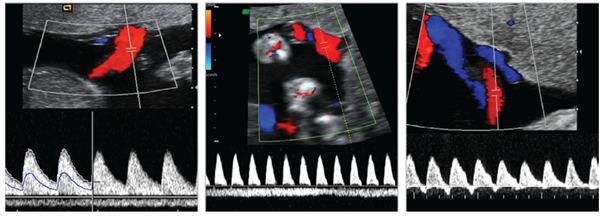

학회가 전하는 초음파 소식 Ultrasound in the Assessment of Obstetric hemorrhage and Postpartum Uterine Abnormalities 2026-02-02 부인과 수술에서 수술 중 초음파(IOUS)의 역할과 최신 임상 응용 2026-01-06 New insights into functional imaging of the placenta 2025-12-01 더보기